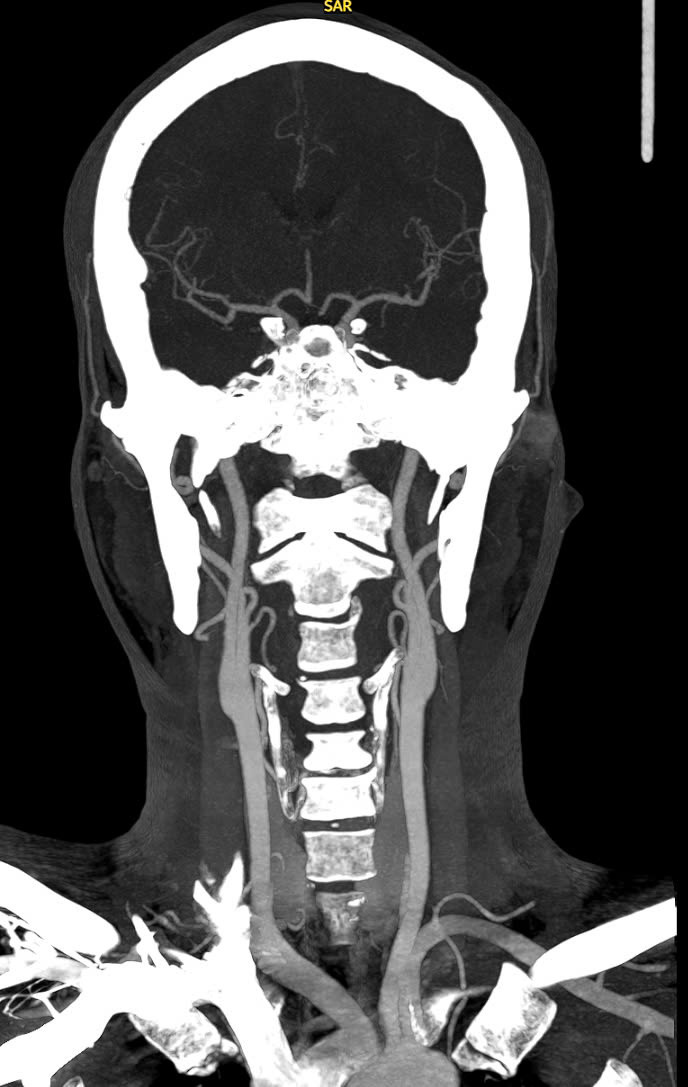

| Chụp sọ não cho bệnh nhân - Ảnh BVCC |

Dựa trên kết quả chụp CT não, các bác sĩ đã xác định anh V. bị đột quỵ nhồi máu não giờ thứ nhất, nghĩa là còn trong thời gian vàng (trước 4,5h sau khi khởi phát) nên anh đã được chỉ định sử dụng thuốc tiêu sợi huyết (rTPA).